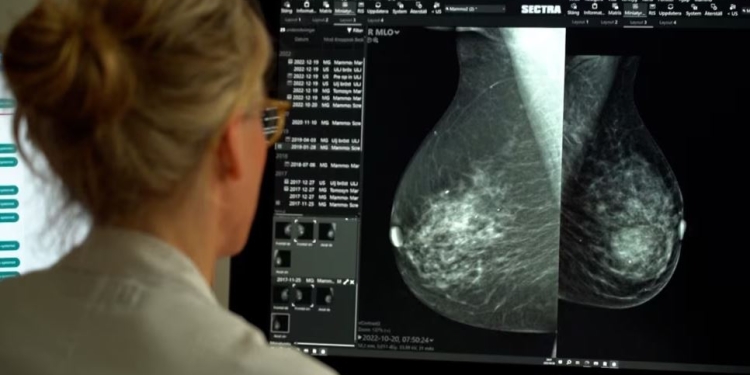

Pesë hulumtuesve të këtij Instituti, Universitetit të Kalifornisë dhe Universitetit të Uashingtonit, u është dhënë qasje në programin komercial të inteligjencës artificiale, i cili në mënyrë retroaktive ka analizuar mamografitë e 116.495 grave që kanë marrë pjesë në programin norvegjez në periudhën 2004 – 2018.

Algoritmi ka arritur të verifikojë se cilat gra kanë pasur rrezik më të madh të zhvillimit të kancerit në gji, madje edhe se cili prej gjinjve ka qenë më i rrezikuar, katër deri në gjashtë vjet para diagnostikimit.

“Ne e kemi vërejtur se gjiri që ka zhvilluar kancer, ka pasur pikë në sistem dyfish më shumë, sesa gjiri tjetër”, ka thënë Solveig Hofvind, gruaja që udhëheq programin për detektim të kancerit në gji përmes programit me inteligjencë artificiale.